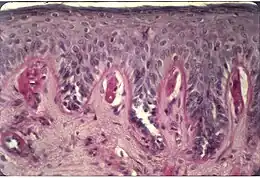

On peut aussi avoir recours à la photothérapie. Il s’agit d’une exposition, aux rayons UVA (PUVA-thérapie) et UVB à spectre étroit. Elle doit être limitée, elle est effectuée en général trois fois par semaine pendant cinq semaines au printemps. Elle provoque un léger épaississement de la peau et développe une mélanogenèse (un bronzage) qui peut renforcer la résistance à l’exposition au soleil[2].